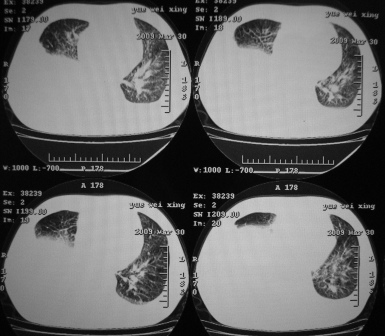

xx 男 43岁

右下叶支气管变窄闭塞,右下叶实变,双肺野弥漫性斑片状影,肺纹理增多增粗,纵隔多发淋巴结肿大,双侧胸水,考虑1双肺继发型结核,右下叶支气管内膜结核,双侧胸水2右下叶中央型肺癌伴右下叶实变,双肺转移,纵隔淋巴转移,双侧胸腔积液3淋巴瘤,请结合病史进一步检查。